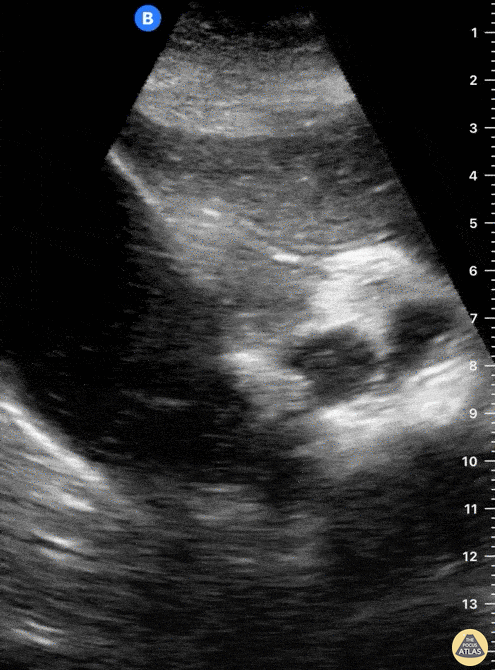

A 65-year-old female with no PMH presented to ED with 6 hour hx RUQ abdominal pain. She reported no associated vomiting or fever. POCUS seen here reveals the cystic duct emerging from the GB neck to then reach a severely dilated CBD. A hyperechoic round structure with posterior shadowing lies inside the CBD, consistent with a diagnosis of choledocholithiasis. Dr. Felipe Urriola Emergency Unit. Puerto Aysen Hospital, Chilean Patagonia.